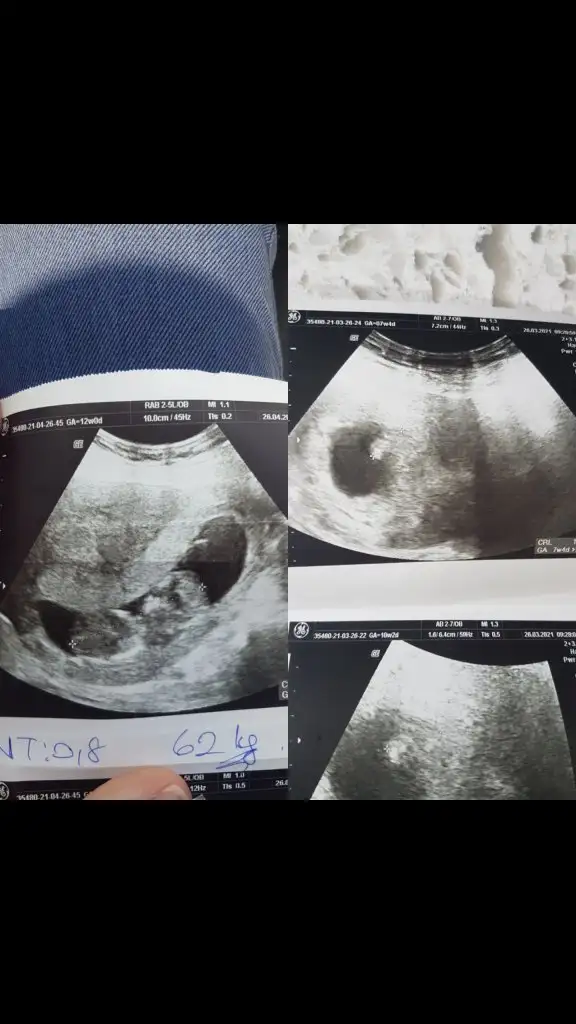

Doktorunuz özeldemiydi, inşallah benmkide feğişir sizinki gibi 12.haftada koz dedi ama 2 kızım var çok isterim oğlum olsun sizinki gibi bir mucizeye ihtiuacım varSelamlar bende eklemek istiyorum 16.5 haftalık aslında 14 haftaya kadar kız demişlerdi bugun ise erkek söylendi

Doktorunuz özelmiydi,Çok teşekkürler. Ramiz teorisine göre de kız demişti arkadaş vlla ne yalan söyleyeyim bende kız istiyordum bi oğlum vardı. Nasip gördük bugün pipiyi 16. Haftadayız değişmez herhalde

Allah bağışlasın canimTsk ederim canim ilgine. Bu platformu bilmiyorum msjlasma nasil yeniyim. 12+2 idik fotoda.

Sağlıkla gelsin oğlusun anketimi oyladinzmiBenim cinsiyetim belli olduIkra meyra ..bidin erkek bir kızım vardı. Cok şükür bide oglusum olacak insallah